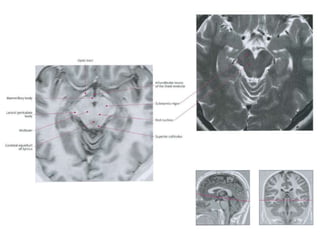

• The tectum (“roof”) is the dorsal part of the

mesencephalon (midbrain).

• Consists of the inferior and the superior colliculi.

– The superior colliculus is involved in preliminary visual

processing and control of eye movements.

– The inferior colliculus is involved in auditory

processing. It receives input from various brain stem

nuclei and projects to the medial geniculate nucleus

of the thalamus, which relays auditory information to

the primary auditory cortex.

– Both colliculi also have descending projections to the

paramedian pontine reticular formation and spinal

cord.

– Collectively the colliculi are referred to as the corpora

quadrigemina.

Red nucleus

• The red nucleus and substantia nigra are

subcortical centers of the extrapyramidal motor

system.

Substantia nigra

• Pigmented layer- melanin granules

• Dorsal to peduncles and ventral to the red

nucleus .

• Composed zona compacta and zona reticulata